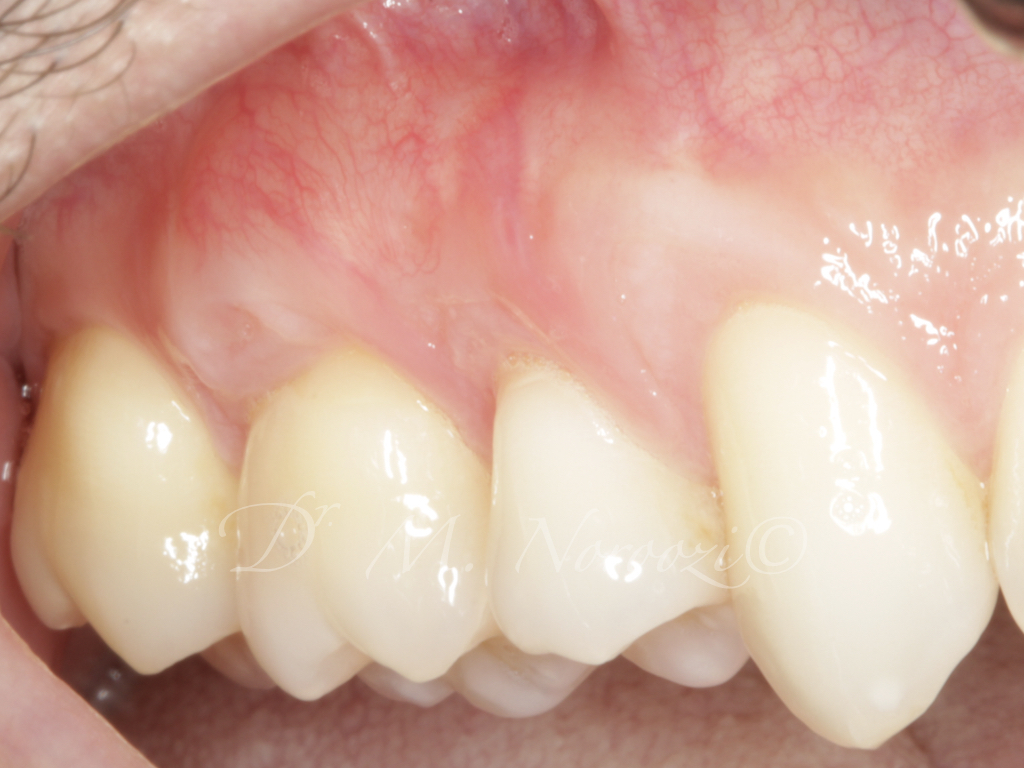

Connective Tissue Gingival Grafting for Gingival Recession